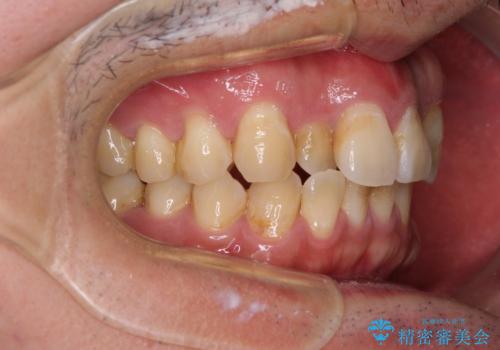

- 虫歯が多く、セラミッククラウンにより虫歯治療を行っている途中で矯正治療をしたいとのことで来院された患者様です。

上顎前歯が舌側に転位しており、なるべく早く楽に矯正したいとのことで、ワイヤー矯正を行うこととしました。